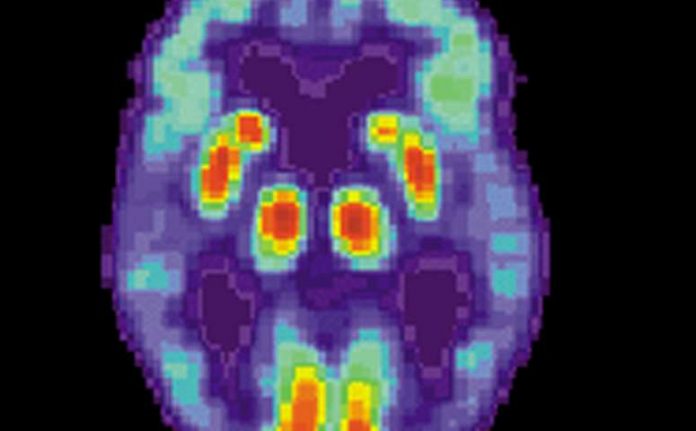

L’étude de Wilber et Benthem, basée sur la mesure des ondes cérébrales dans des modèles murins de la maladie, a donné aux chercheurs un certain nombre de nouvelles idées sur la maladie d’Alzheimer, notamment sur la façon dont deux parties du cerveau – le cortex pariétal et l’hippocampe – interagissent pendant le sommeil, ce qui peut contribuer aux symptômes ressentis par les patients atteints de la maladie d’Alzheimer, tels que les troubles de la mémoire et de la cognition, et le fait de se perdre dans un nouvel environnement.

Pendant ces périodes de relecture de la mémoire, ils ont découvert que les souris modélisant les aspects de la maladie d’Alzheimer chez l’homme avaient des interactions fonctionnelles altérées entre l’hippocampe et le cortex pariétal.

La formation de l’hippocampe est cruciale pour le stockage des souvenirs “épisodiques” – un type de mémoire à long terme d’une expérience passée – et est considérée comme importante pour aider d’autres parties du cerveau à extraire des connaissances généralisées de ces expériences personnelles.

Il est surprenant de constater qu’un meilleur prédicteur de la performance et de la première déficience n’était pas la “répétition de la mémoire” en soi, mais plutôt la force relative du couplage post-apprentissage entre deux régions du cerveau connues pour être importantes pour l’apprentissage et la mémoire : l’hippocampe et le cortex pariétal”, a déclaré M. Wilber.